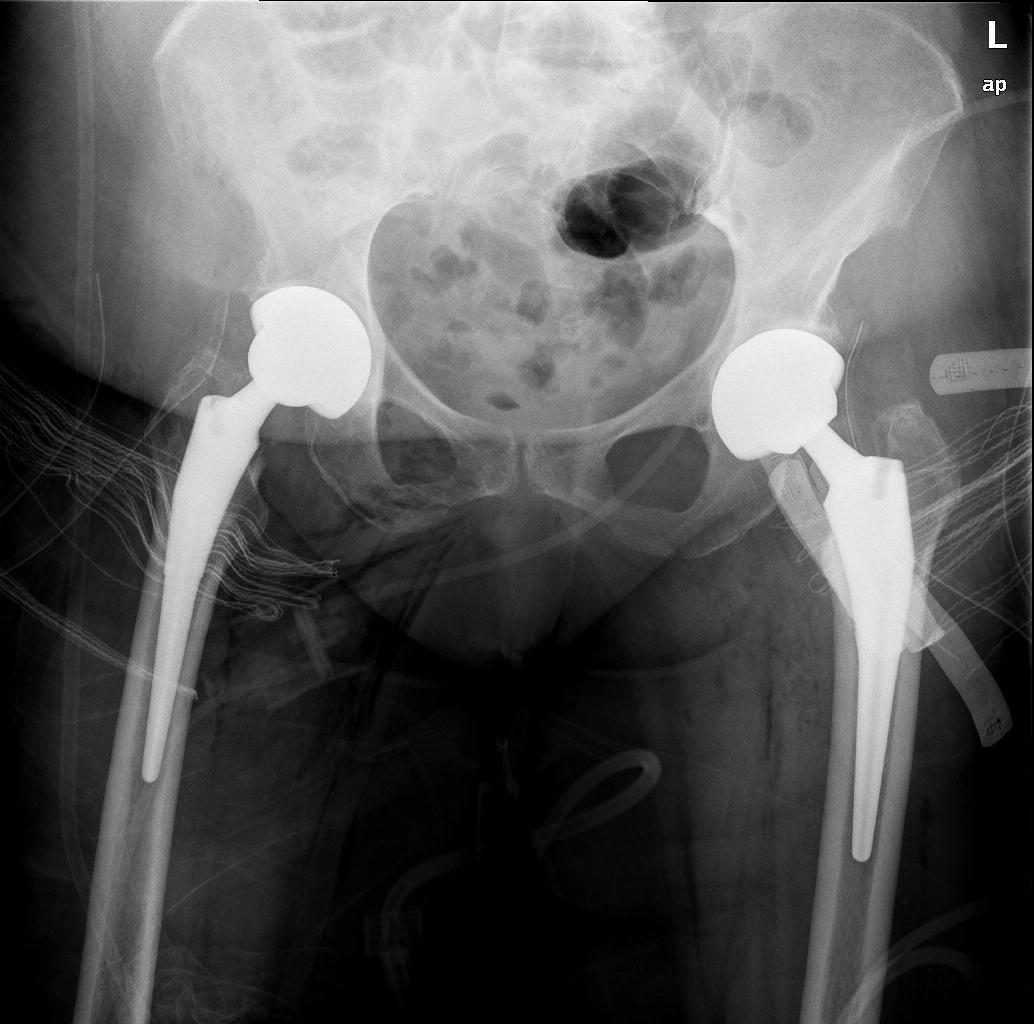

Τα περισσότερα εμφυτεύματα σήμερα έχουν παρόμοια σχέδια και σχήματα, αλλά ο γιατρός σας θα καθορίσει ποια σχέδια λειτουργούν καλύτερα για το σώμα σας. Αυτά τα εμφυτεύματα είναι κατασκευασμένα από κοβάλτιο χρώμιο ή τιτάνιο. Μια μεταβλητή που παραμένει ακόμα είναι η επιφάνεια φόρτισης. Η επιφάνεια φόρτισης είναι η σφαίρα, η κεφαλή και η επένδυση που προσκολλώνται στο μηριαίο στέλεχος, και το κυπέλιο, η το κοτυλιαίο εμφύτευμα που στερεώνεται στο οστό. Η κεφαλή μπορεί να αποτελείται είτε από μέταλλο (κράμα χρωμίου κοβαλτίου) είτε από κεραμικό και η επένδυση μπορεί να είναι από πλαστικό (πολυαιθυλένιο), μέταλλο ή κεραμικό. Η κεφαλή και η επένδυση μπορούν στη συνέχεια να χρησιμοποιηθούν σε διαφορετικούς συνδυασμούς και ονομάζονται για τον αντίστοιχο συνδυασμό επένδυσης κεφαλή (μέταλλο σε πολυ, κεραμικό σε πολυ, κεραμικό σε κεραμικό κ.λπ.).

Το 2023, τα περισσότερα χρησιμοποιούσαν επένδυση πολυαιθυλενίου με κεραμική κεφαλή, ενώ άλλοι συνδυασμοί χρησιμοποιούνται με μικρότερη συχνότητα. Μπορείτε να συζητήσετε αυτές τις διαφορές με τον χειρουργό σας για να προσδιορίσετε ποιο εμφύτευμα είναι καλύτερο για εσάς.